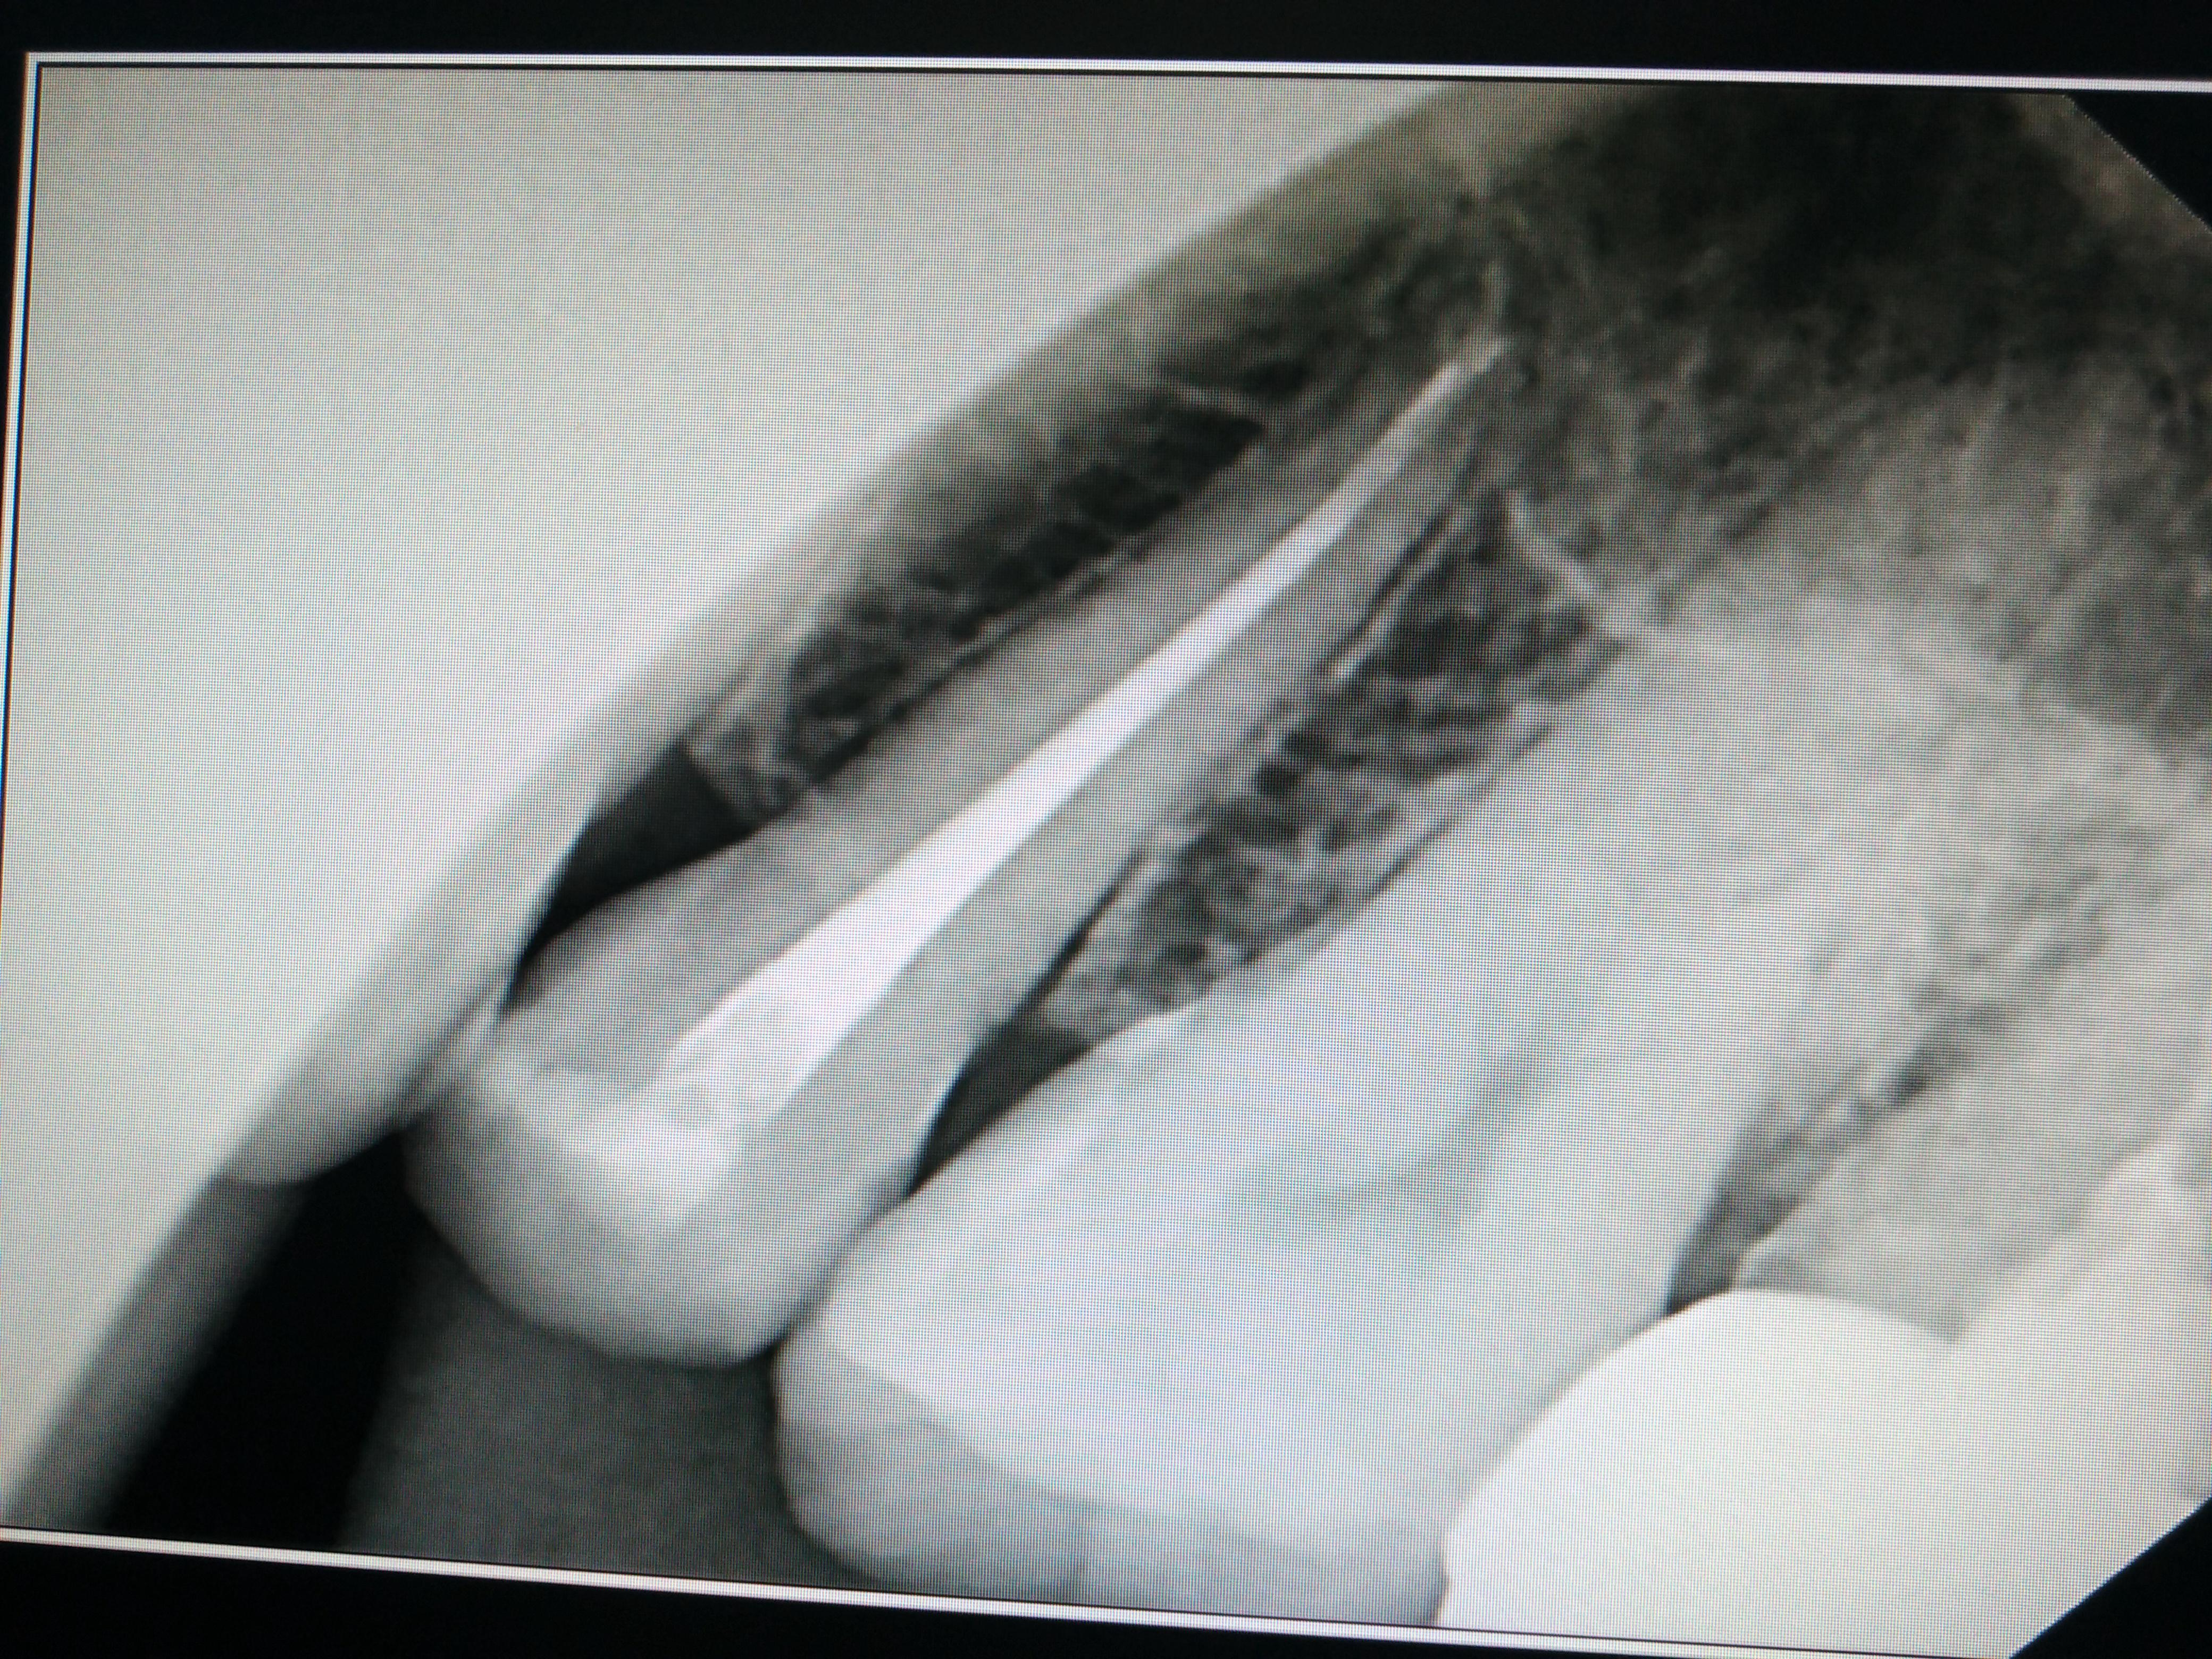

牙片看根管侧穿底穿和根裂

根管治疗三个月了还是自发痛,现疼痛减轻不少,偶尔一跳一跳的痛,偶尔酸;摇患牙酸酸的感觉,请大家看看该牙有异常吗,暂封的药物,还未根充。小牙片从左数第一颗,是上牙五号。谢谢!

根折了,很明显啊,看不出来吗?

看着不像是底穿